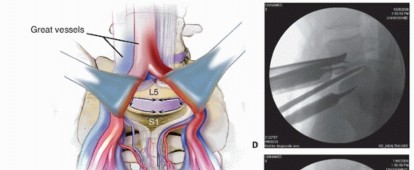

At L5-S1, retract the left common iliac artery and vein to the patient's left and the right common iliac artery and vein to the right. At levels above L5-S1, the aorta and inferior vena cava must be mobilized to the patient's right.

The great vessels can be held in their retracted position using handheld Hohmann retractors, custom-designed pins, or Kwires, all of which can be advanced directly into the vertebral bodies (virtually eliminating the risk of vessel migration into the field of interest) (TECH FIG 1B).

- TECH FIG 4 • AP (A) and lateral (B) fluoroscopic images showing midline positioning and screw trajectories of stand-alone ALIF device.

Typically, a single interbody cage that spans the disc space is selected, with graft material packed on both sides within the implant. This is positioned in the center of the interspace using product-specific instruments (TECH FIG 4A).

Locking screws are directed cephalad and caudad either through the cage device or through a metal faceplate that attaches to the cage (TECH FIG 4B). Knowledge of productspecific screw trajectories and starting points is paramount as they may be either symmetric about the midline or translated left or right to allow safe passage of the drill between the iliac vessels. - Adjunct Treatments